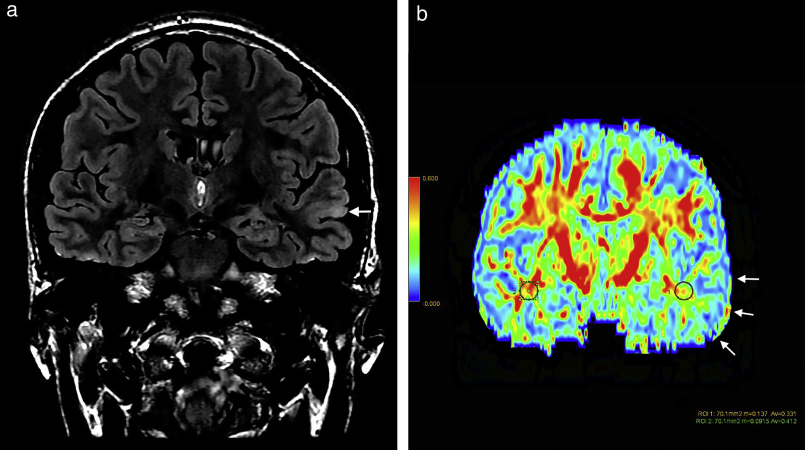

A displasia cortical focal é uma malformação no córtex cerebral que provoca lesões sutis e difíceis de detectar, mesmo com exames de ressonância magnética de alta resolução. Pacientes com essa condição frequentemente não respondem a tratamentos com anticonvulsivantes, tornando a cirurgia para remoção das áreas afetadas a única opção viável para aliviar os sintomas. No entanto, a localização precisa dessas lesões é um desafio, o que dificulta o sucesso do procedimento cirúrgico.

A MELD Graph foi desenvolvida utilizando técnicas avançadas de aprendizado de máquina e analisou dados de ressonância magnética de 1.185 indivíduos, incluindo 703 pacientes com DCF e 482 pessoas sem a condição. O algoritmo da ferramenta conseguiu detectar 64% das anormalidades cerebrais que haviam passado despercebidas por radiologistas especializados. Com isso, espera-se que a tecnologia beneficie mais de 4 milhões de pessoas em todo o mundo que sofrem com essa forma grave de epilepsia.

Um caso emblemático foi o de um menino de 12 anos que sofria com crises diárias e havia tentado nove medicamentos sem sucesso. A ferramenta identificou uma lesão cerebral sutil que havia passado despercebida pelos radiologistas. Segundo Luca Palma, do Bambino Gesù Children’s Hospital, na Itália, a MELD Graph não apenas auxilia na identificação de pacientes candidatos à cirurgia, mas também no planejamento do procedimento, reduzindo riscos e custos.